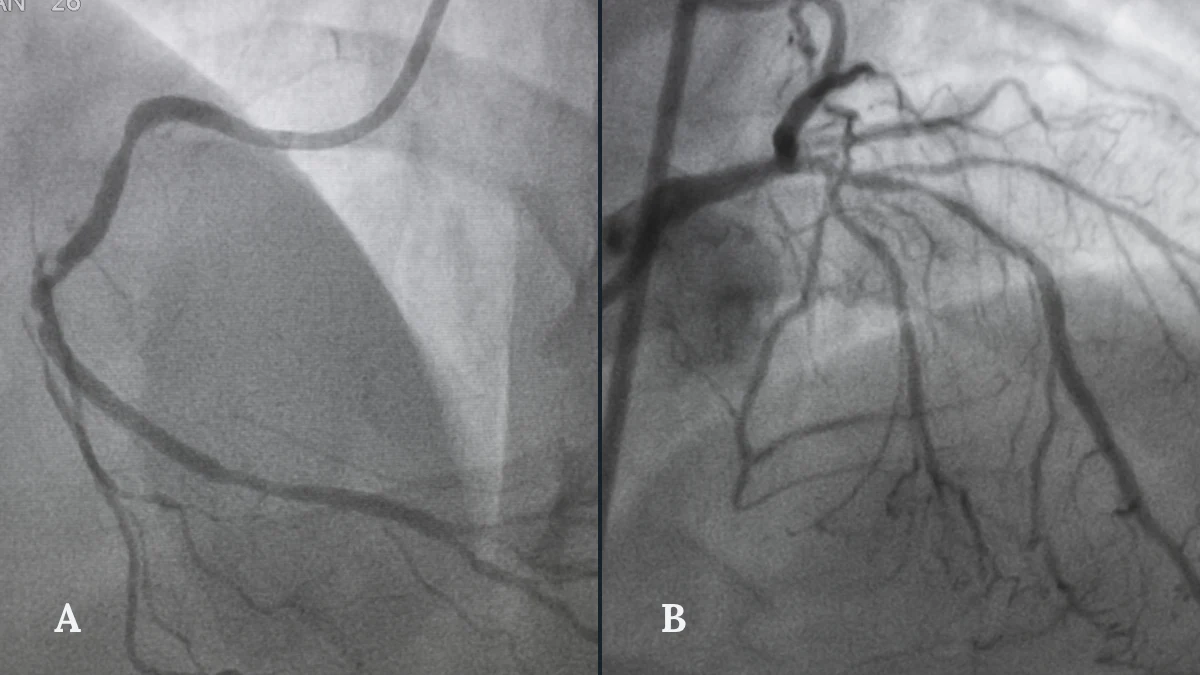

A coronary angiogram

During an angiogram, a thin flexible catheter is passed into the coronary arteries and a small amount of contrast dye is injected. The dye makes the arteries visible under X-ray, allowing your cardiologist to see exactly where plaque has built up and where blood flow is restricted. This is the investigation that forms the foundation of your Heart Team’s decision.

Not all coronary disease is equal. A single, straightforward blockage in one artery is a fundamentally different clinical problem from three heavily calcified blockages across multiple vessels, one of which sits at a critical branching point where two arteries divide. The SYNTAX score gave the field a standardised, reproducible way to measure coronary complexity from the angiogram, the X-ray map of your coronary arteries, and express it as a single number.